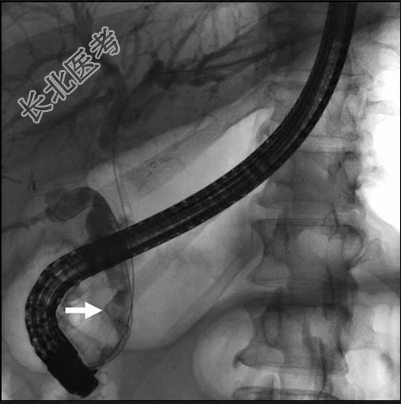

由于患者疑似急性上行性胆道炎,隧开始静脉应用哌拉西林/他唑巴坦治疗。内镜逆行胰胆管造影术(ERCP)中胆道造影显示远端插入的长胆囊管残端充盈缺损,提示残留结石导致部分胆道梗阻。

隧行括约肌切开术,置入9-12 mm球囊探查总胆管,在胆囊管插入处遇中度阻力。术后CBD内未发现充盈缺损也未发现结石。随后选择性进行胆囊管置管并置入球囊,取出一较大胆管结石。球囊胆管造影显示整个胆道,包括胆囊管残端无残余充盈缺损,胆汁和造影剂引流良好,最终确诊为胆囊切除术后Mirizzi综合征(PCMS)。